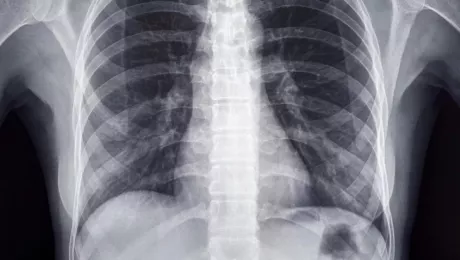

Человеческий скелет является удивительным инженерным достижением природы, обеспечивая как жесткость, так и гибкость. Одним из его наиболее уникальных аспектов является структура ребер. Вместо единой сплошной конструкции, наши ребра разделены, позволяя телу выполнять множество жизненно важных функций.

Ребра представляют собой дугообразные кости, соединенные с грудной костью спереди и с позвоночником сзади. Такая структура формирует грудную клетку, играющую ключевую роль в защите сердца, легких и других важных органов. Между соседними ребрами находятся межреберные мышцы, которые при сокращении и расслаблении способствуют дыханию.

Разделенные ребра позволяют грудной клетке расширяться и сжиматься, что необходимо для процесса дыхания. Во время вдоха межреберные мышцы сокращаются, поднимая ребра и увеличивая объем грудной полости, создавая пространство для наполнения легких воздухом. При выдохе происходит обратный процесс, способствующий удалению воздуха из легких.